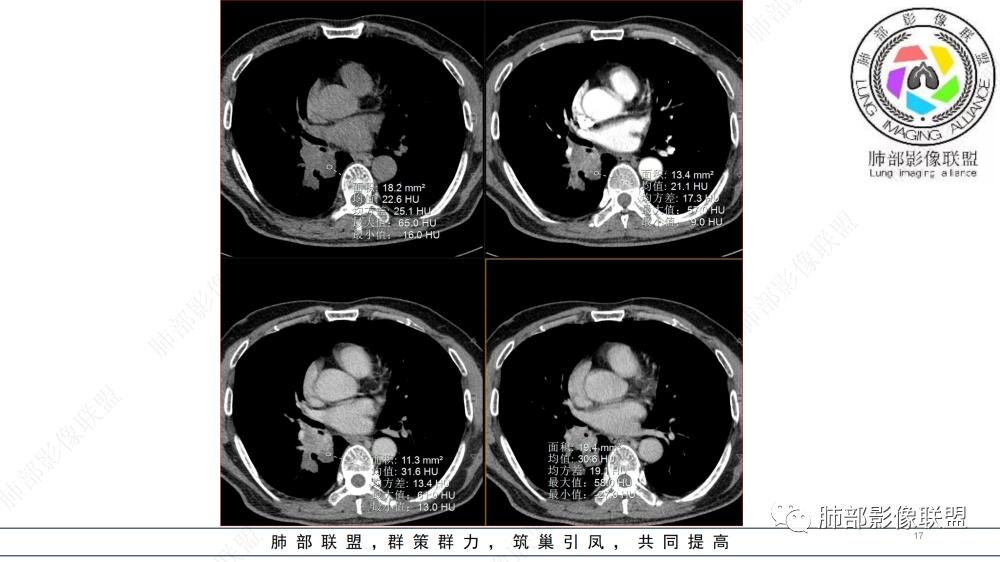

中老年男性,右肺下叶背段支气管内新生物,近端可见息肉样突起,远端沿分支支气管生长堵塞,肺门口病灶增强后明显强化,峰值达140hu,远端部分强化不明显考虑粘液栓,考虑典型类癌,鉴别鳞癌。

右支气管腔沿管壁占位,病灶不彻底的坏死是不均一强化,胆碱脂酶异常升高,首选鳞癌!鉴别类癌

气管截断,血管破坏,跨壁内外生长,阻塞性炎症,定性恶性,明显强化,首先考虑类癌,鉴别鳞癌

中年男性,病史半年,不发热,有咳血,右肺门不规则肿块,向支气管内突出,不均匀强化,局部强化明显,远端有小尾巴,考虑恶性肿瘤,类癌、小细胞、鳞癌。